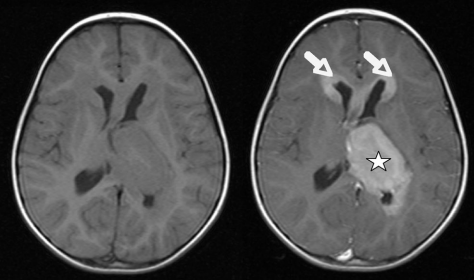

图 1 术前轴位对比增强 T1 加权成像。病变呈脑内生长,并延伸至左侧脑室枕角(星号)。双侧额叶在脑室额角周围受浸润(箭头)。